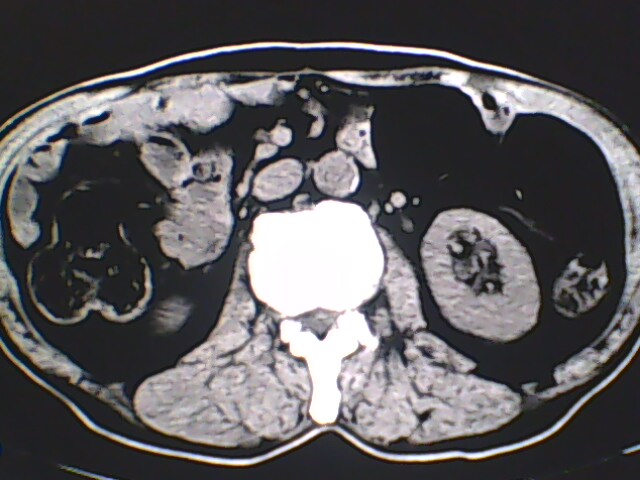

男,56岁,高血压,临床怀疑肾上腺问题,肝脏怎么那么高啊?能描述一下么?

右侧膈膨升,间位结肠,胸腰椎退行性骨关节病,右侧肾上腺可疑增生(图像颗粒太粗,窗太窄,不好看)。

支持 右侧膈膨升,间位结肠;胸腰椎退行性骨关节病;双侧肾上腺可疑增生。

右侧膈膨升,间为结肠